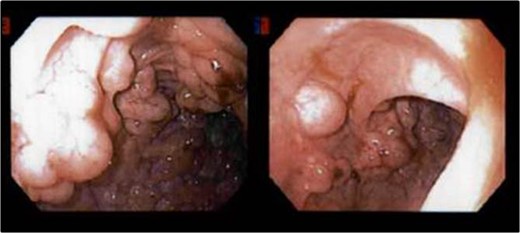

In this case report, we describe a patient who initially presented with symptomatic pneumatosis coli and pneumoperitoneum of undetermined etiology. Despite the imaging findings, his entire clinical picture did not warrant emergent surgical intervention, and he was managed conservatively as an inpatient. He was discharged home and additional work-up was performed on an outpatient and elective basis, revealing multiple sigmoid hyperplastic polyps without evidence of transmural colonic perforation.

Pneumoperitoneum in association with PCI can be secondary to viscus perforation or ruptured intramural cysts [3]. When this patient initially presented to the ED, he had free air on CT concerning for colonic perforation. However, further work-up determined the source of pneumoperitoneum was likely from ruptured intramural cysts as there was no evidence of gross transmural perforation intraoperatively and on final surgical pathology of the sigmoid colon. This correlates with his benign clinical picture.